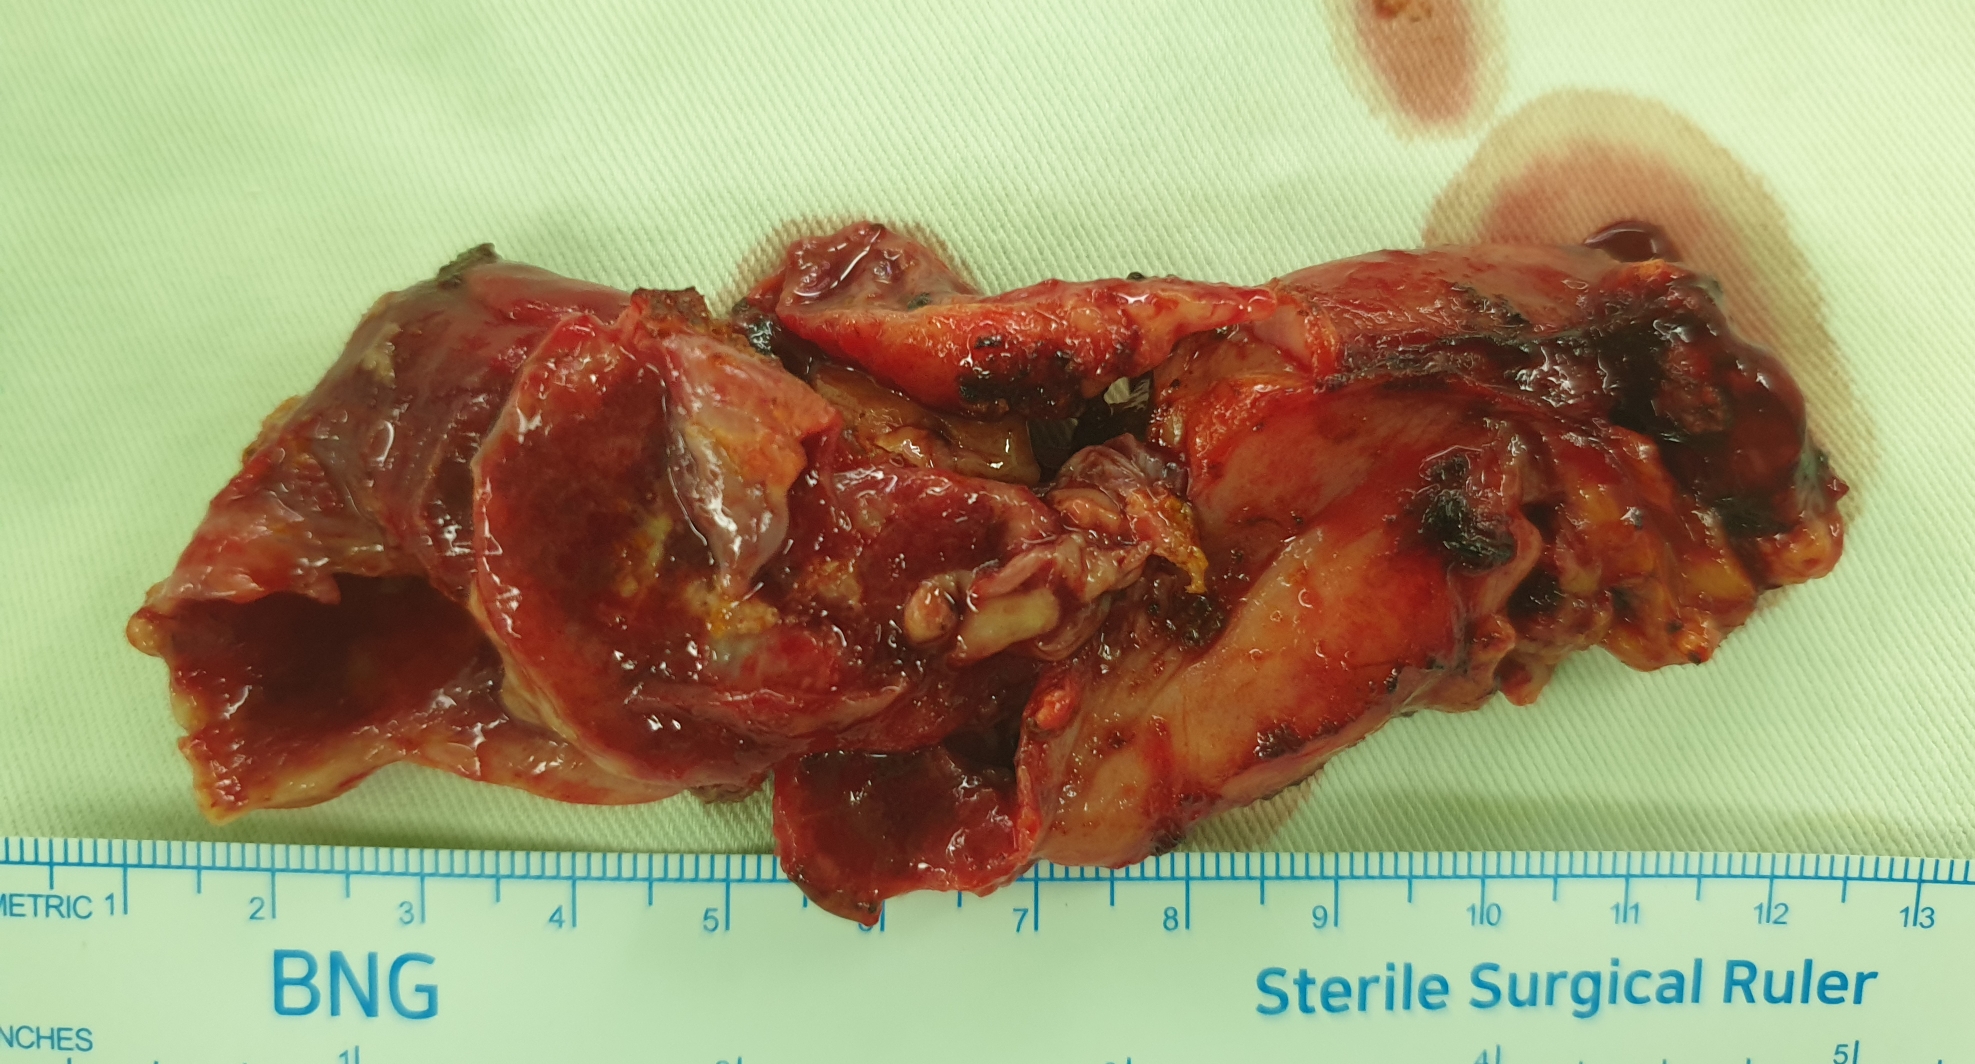

방금 복강경 담낭절제술을 시행했습니다.

담낭이 염증으로 천공되어 담즙이 복강내에 퍼져있는 복막염 소견이었습니다.